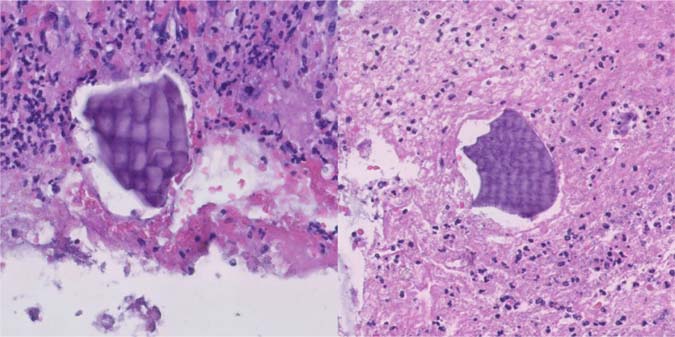

Figure 5: Medium power image of fibrinopurulent exudate, with sevelamer (left) and Kayexalate (right) crystals (Hematoxylin and eosin, 10× magnification).

Figure 6: High power images of fibrinopurulent exudate and embedded Kayexalate crystals with purple color and typical fish-scale pattern (Hematoxylin and eosin, 20× magnification).

Figure 7: High power images of fibrinopurulent exudate and embedded sevelamer crystals with yellow color and fish-scale pattern (Hematoxylin and eosin, 20× magnification).

Figure 8: High power image of Kayexalate (left) and sevelamer (right) crystals with differential staining patterns (Kinyoun, 20× magnification).